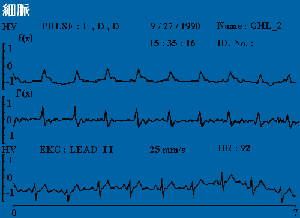

脈診波形

代脈_0020765003

平脈_0020765001

弦脈_0020765002

弦滑脈_0020765004

促脈_0020765001

洪脈_0020765002

細脈_0020765002

結脈_0020765004

滑脈_0020765001

數脈_0020765005

遲脈_0020765005

澀脈_0020765001

濡脈_0020765003